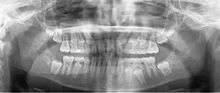

A panoramic radiograph is a panoramic scanning dental X-ray of the upper and lower jaw. It shows a two-dimensional view of a half-circle from ear to ear. Panoramic radiography is a form of tomography; thus, images of multiple planes are taken to make up the composite panoramic image, where the maxilla and mandible are in the focal trough and the structures that are superficial and deep to the trough are blurred.

A dental panoramic radiograph, showing the maxilla and mandible, all the teeth including the "wisdom teeth," the frontal and maxillary sinuses, the nasal cavity and the temporomandibular joint and other near by head and neck anatomy. | |